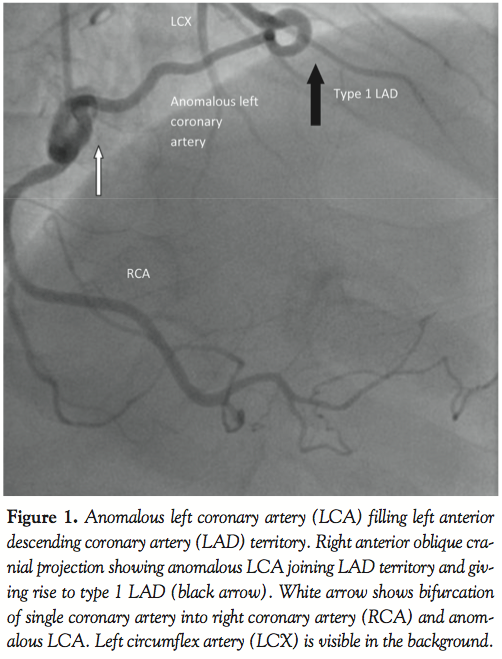

A 59-year-old man with a history of hypertension, family history of premature coronary artery disease and atypical chest heaviness was referred to exercise stress test. After achieving 89% target heart rate at a workload of 9 metabolic equivalents using Bruce protocol, 1–1.5 mm horizontal ST depressions were seen in the lateral leads. Coronary angiogram revealed a single coronary artery originating from the right sinus of Valsalva; this artery bifurcated into a right coronary artery and an anomalous left main coronary artery. Multi-detector row computed tomography confirmed the same findings. The anomalous left coronary artery followed a pre-pulmonary course anterior to the pulmonary trunk to supply the anterior descending, diagonals and circumflex artery. There was no evidence of an inter-arterial course, which is considered malignant. The coronary arteries were free of atherosclerotic disease. Stress myocardial perfusion imaging showed no inducible ischemia. Echocardiogram showed normal left ventricular function.